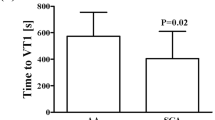

Univariate analysis comparing two groups of SCA patients based on their %\({\dot{V}O}_{2peakth}\) at BL4

The study population was then divided into two groups based on the median of the occurrence of BL4 expressed as %\({\dot{{\text{V}}}{\text{O}}}_{2peakth}\) that was calculated at 39%. Fourteen patients constituted the lower exercise level group (BL4 < 39% group, %\({\dot{{\text{V}}}{\text{O}}}_{2peakth}\)= 34.4 ± 5.4%) and 15 patients were included in the upper exercise level group (BL4 ≥ 39% group, %\({\dot{{\text{V}}}{\text{O}}}_{2peakth}\) = 46.2 ± 6.8%). Baseline clinical, biological and echocardiographic data of these two groups are reported in Table 3. In univariate analysis, hemoglobin (8.1 ± 1.1 vs. 9.2 ± 1.1 g dL−1, p = 0.009) and beta-blocker use [7 (50%) vs. 1 (13%), p = 0.03] were the only two baseline variables associated with early occurrence of BL4. None of the echocardiography data assessed at rest could discriminate the two groups. As expected, the BL4 < 39% group developed less power output and MET at BL4 than the BL4 ≥ 39% one (33 ± 4.7 vs. 42.8 ± 9.6% of \({\dot{{\text{W}}}}_{maxth}\), p = 0.002 and 3.6 ± 0.6 vs. 4.7 ± 1 MET, p = 0.003, respectively; Table 4). Notably, the BL4 < 39% group showed abnormal diastolic adaptation at BL4 as assessed by the normalized to baseline e′ and E/e′ (e′BL4/e′rest = 1.4 ± 0.2 vs. 1.6 ± 0.3, p = 0.039 and E/e′BL4/ E/e′rest = 1.2 ± 0.2 vs. 1.0 ± 0.2, p = 0.003). The BL4 < 39% group also had a trend for poorer peripheral oxygen extraction at BL4 (AV-O2Δ: 112 ± 33 vs. 147 ± 59 mL L m−2, p = 0.07) while increases in blood pressure, heart rate, and cardiac output were similar between the two groups (Table 4).

Multivariate analysis using logistic regression

Baseline hemoglobin, beta-blocker use, oxygen saturation at rest, AV-O2Δ at BL4, and BL4 to baseline ratio of e′ and E/e′ were entered into multivariate analysis (Table 5). Baseline hemoglobin (OR = 3.5 [1; 13], p = 0.05) and E/e′ ratio (OR = 10–3 [10–4; 0.6], p = 0.04) were independently associated with early occurrence of BL4.

Correlations between %\({\dot{V}O}_{2peakth}\) at BL4 and parameters of interest based on group comparison